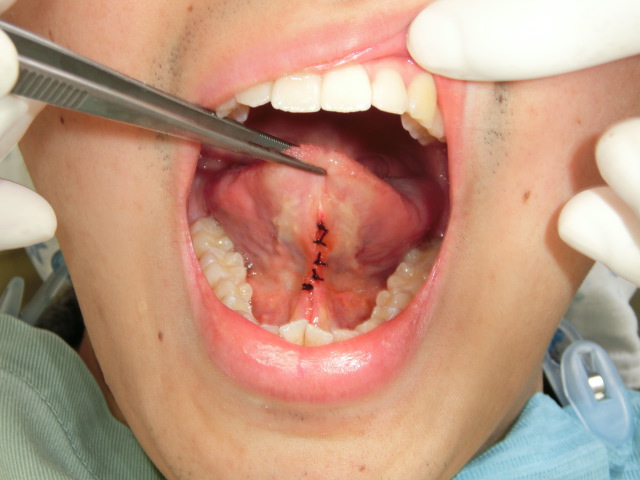

症例2:舌小帯形成術

小学校高学年以上であれば、手術は15分ほどで終わります。

一般的には舌小帯に横切開を加え、舌小帯を切離して菱形となった切開創の舌下面と口腔底の部分を縫合する(舌小帯切断伸展術)ことによって、舌運動制限を解除します。

手術に際しては、舌下小丘の損傷や舌小帯の過剰切離などに注意します。